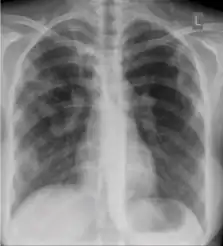

5. Hilar or mediastinal lymphadenopathy (bihilar lymphadenopathy) - Enlargement of lymph nodes in one or both hila or within the mediastinum, with or without associated atelectasis or consolidation.

-

Chest x-ray showing bilateral hilar adenopathy of primary pulmonary TB